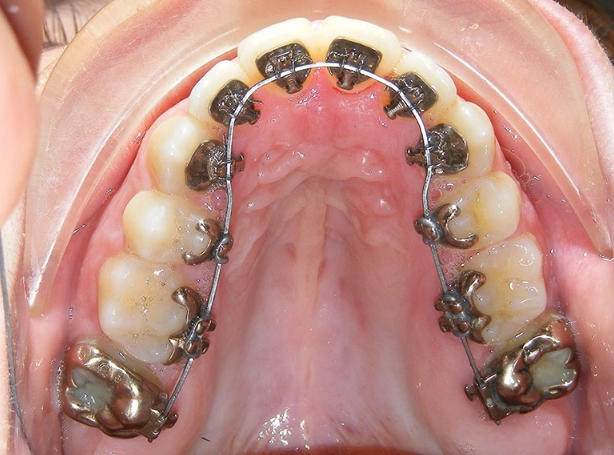

| Periodontal Treatment | A periodontal abscess from gum disease. | Deep cleaning (scaling/root planing) below the gumline to remove tartar and bacteria. | Manages gum disease and the abscess. Requires ongoing periodontal maintenance. |